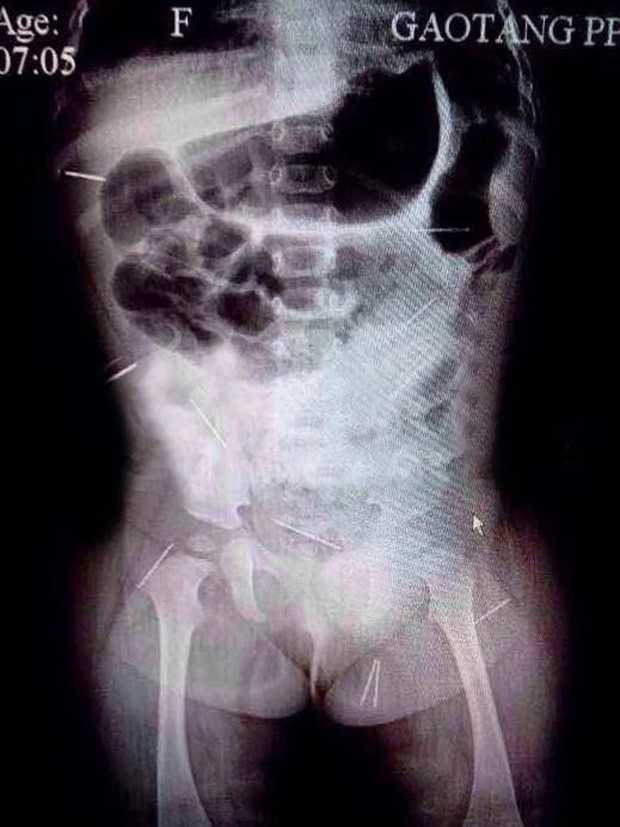

Sự thật bị phanh phui khi bác sĩ đưa cho gia đình xem tấm phim chụp X-quang của đứa trẻ. Vợ chồng chị Hương ngã quỵ tại chỗ, lòng đau không từ ngữ nào tả xiết khi trông thấy khắp cơ thể Tử Huyên có đến 12 cây kim đâm vào.

Trong hình chụp cho thấy, những chiếc kim bị đâm vào mông, khoang bụng, xương chậu và nhiều bộ phận quan trọng khác trên người cô bé đáng thương. Nhận thấy vụ việc không hề đơn giản. Gia đình Tử Huyên đã báo cảnh sát can thiệp.

Sau 3 tiếng rưỡi phẫu thuật với sự hợp tác của 9 khoa, toàn bộ 12 cây kim thép đã được lấy ra ngoài. Trong số 12 cây kim, có 4 cây là kim may vá, còn lại là kim y tế và thậm chí có nhiều cây kim đã bị rỉ sét. Tử Huyên sau đó đã bình phục rất tốt, ai cũng vui mừng thở phào nhẹ nhõm.